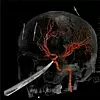

På sykehuset University of Kansas Health System, oppdaget legene at kniven hadde satt seg så dypt inn i hodeskallen at knivspissen lå helt inntil en av pulsårene hans i hjernen, som tilfører blod til hjernen, hodet og nakken.

Denne 3D-grafikken viser hvordan knivspissen var presset inntil pulsåren til Gregg. Foto: The University of Kansas Health System / AP

Denne 3D-grafikken viser hvordan knivspissen var presset inntil pulsåren til Gregg.

Selv om kniven ikke stakk hull på blodåren da uhellet inntraff, var faren for at det likevel kunne skje under operasjonen stor - men utrolig nok gikk operasjon knirkefritt, og blodåren forble intakt.